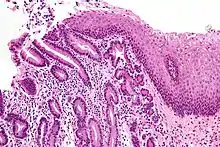

Barrett's esophagus is an abnormal change in the cells of the lower esophagus, thought to be caused by damage from chronic stomach acid exposure.